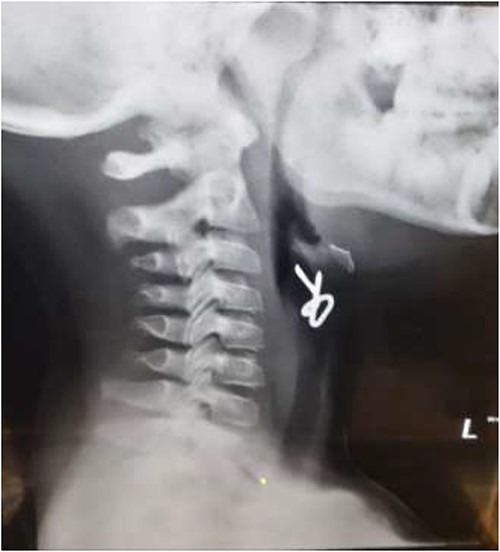

The first case is of a 7-year-old child presenting with a history of barbed wire inhalation. X-ray imaging of his neck and chest showed a radio-opaque object visible in the upper airway with sharp edges (Figs 1 and 2). Due to the position of the foreign body, endotracheal intubation was not feasible. A trial of apnoeic oxygenation using high-flow nasal oxygenation was used as an alternative, and this allowed for an unobstructed view of the larynx, facilitating the safe removal of the foreign body (Fig. 3).

AP chest radiograph showing the sharp-edged radio-opaque object.